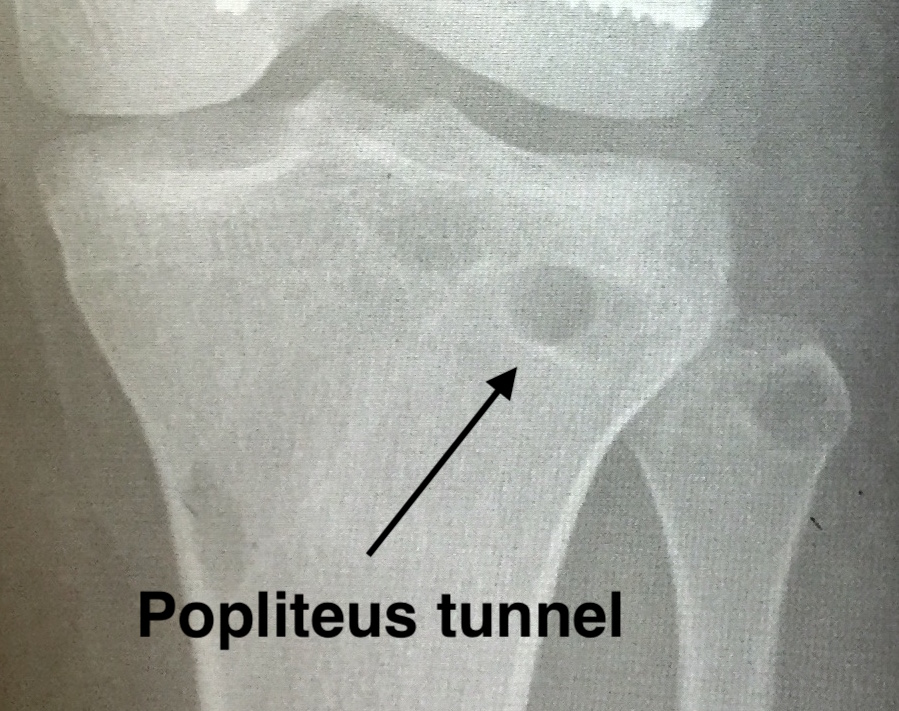

Popliteus tibial tunnel

- anterior entry point is distal and medial to gerdy's tubercle, below tibial plateau

- create posterior window

- anterior to lateral head of gastrocnemius, posterior to knee capsule, above LHB

- insert retractor under lateral head of gastrocnemius to protect vascular structures

- identify and ligate the lateral inferior geniculate artery

- identify with a finger the proximal tibio-fibular joint

- the posterior tunnel must exit medial to this joint, below tibial plateau

- at approximate site of the popliteus musculotendinous junction

- pass beath pin anterior to posterior

- drill to 9 mm

Popliteus tunnel 1Popliteus tunnel 2